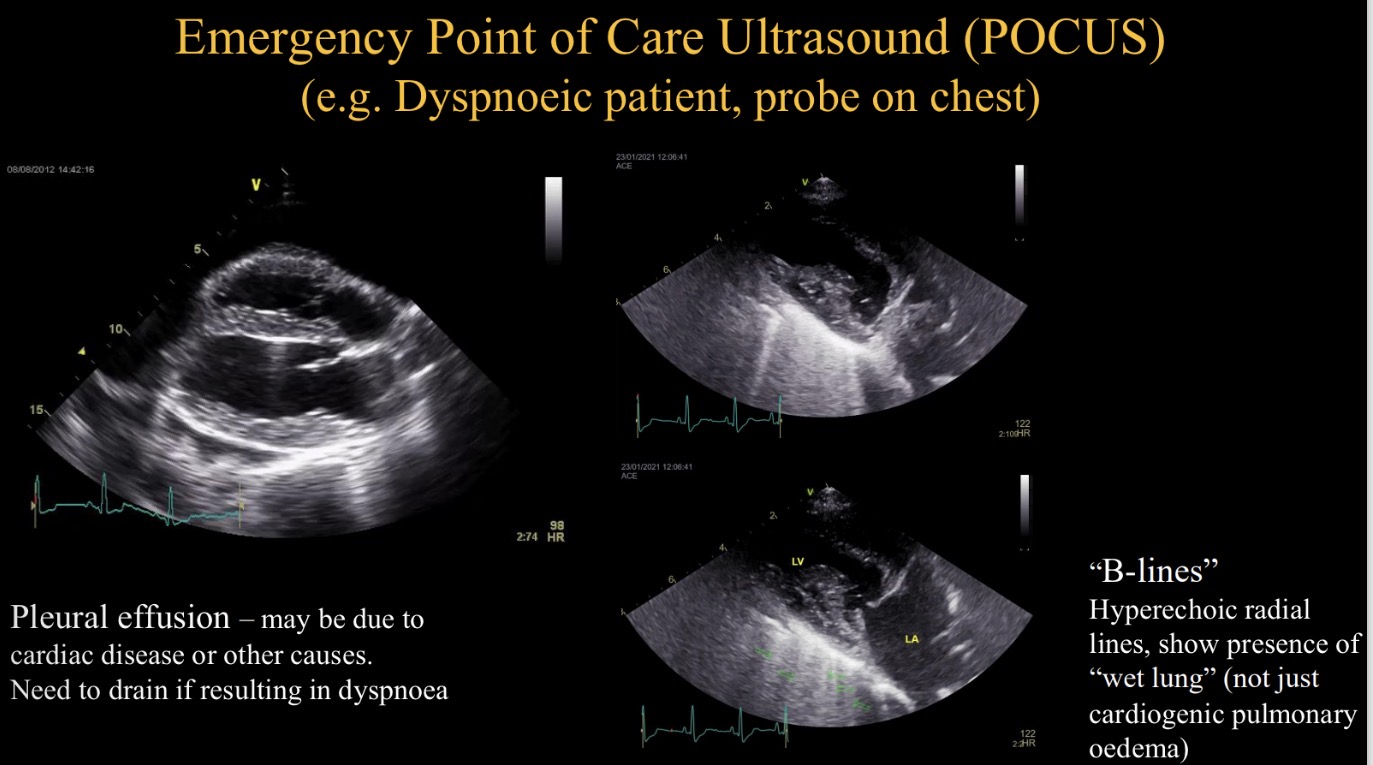

POCUS stands for

Emergency point of care US

Purpose of POCUS in dyspnoeic animal

Identify pleural effusion + drain

Identify hyperechoic lines (B lines)